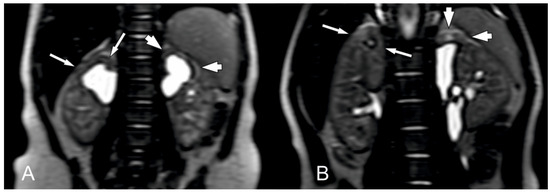

3.2. Magnetic Resonance Urography